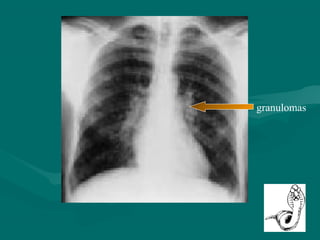

Patogenia

 Granulomas eosinofílicos

granulomas

Patogenia  Niños  Reaccióninflamatoria  Granulomas eosinofílicos  Linfocitos y células epitelioides gigantes  Liberación de antígenos  Elevación de IgE e IgG